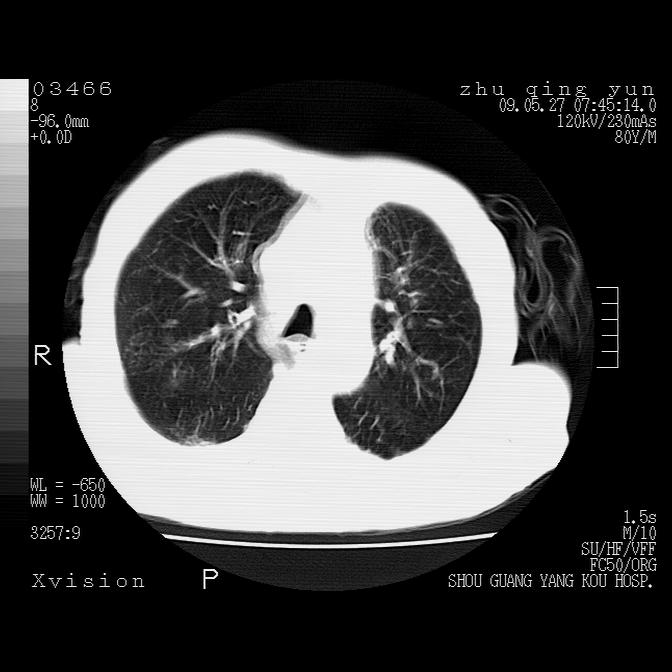

1)考虑左肺中央型肺癌并阻塞性肺炎,后下纵隔受侵伴纵隔淋巴结转移。2)双侧少量胸腔积液,胸膜增厚。3)心包积液。

左肺下叶见多发片状及结节状病灶,左肺基底段支气管闭塞,纵隔内见多发淋巴结肿大,纵隔向左侧移位,左侧胸廓变小。应该是左肺下叶中心型肺癌,纵隔淋巴结转移,左侧肺内转移,左肺基底段肺不张,阻塞性肺炎。

1)考虑左肺中央型肺癌并左肺下叶阻塞性肺炎、不张;左胸膜腔积液、心包积液、纵隔淋巴结转移;癌肿累及左心房。2)左心室大。冠状动脉壁钙化斑。

恶性占位是肯定的,并累及心包并纵隔淋巴结转移/左肺癌性淋巴管炎/肺部感染。是中心性或纵隔型肺癌,还是后纵隔恶性占位,还是食道中下段癌或食道受累需鉴别。

支持以上,左肺肿块应该是周围型吧,考虑左下肺周围型肺癌伴肺内转移,阻塞性肺炎,纵隔淋巴转移,左侧胸膜及心包转移